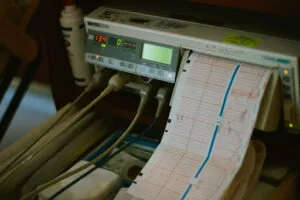

For those who work in cardiology, EKG machines are life saving pieces of equipment, helping to diagnose

Everyday EKGs are being performed to help doctors assess their patients’ health and well-being. This test has

An Electrocardiograph Machine with Innovative Interpretation Software An electrocardiograph machine tracks the electrical activity of a patient’s